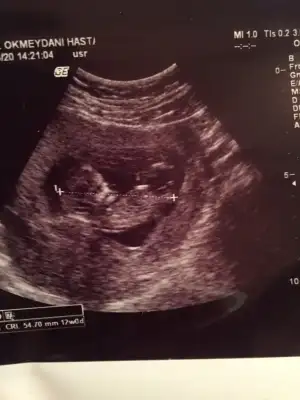

ikili tarama sonrası. Sizce cinsiyeti nedirr? Doktor bi tahmin de bulundu ama daha erken tabi ☺️☺️

Usg net değil emin olmadım başka usg de paylaşın 12 13 hafta olursa şimdilik sanki erkek gibi gibi 😬

Kız sanki burada nubu ne dik nede paralel karşıya bakıyor 😊 önceki usgde erkek gibiydi 😄

😂 Tahminim kız ama daha tam oluşmamış üç haftası var oluşması icin dedi doktor.tabi ki hayırlısı olsun saglıklı hayırlı evlat olsun ama gönlümden gecen kız olması bakalım bekleyip görücez.tesekkürler tahmininiz için ❤️